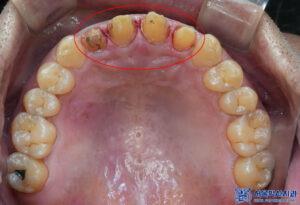

육안으로 확인해 보았을 땐

특별한 이상이 없어

제거를 하고 확인해 보니,

내부로 충치가 생긴 것을

확인할 수 있었습니다.

이로 인해 불편감을

느끼고 계셨을 것으로

예상하였습니다.